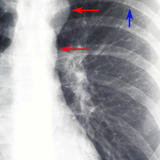

clam shell ASD lat

(diff patient)